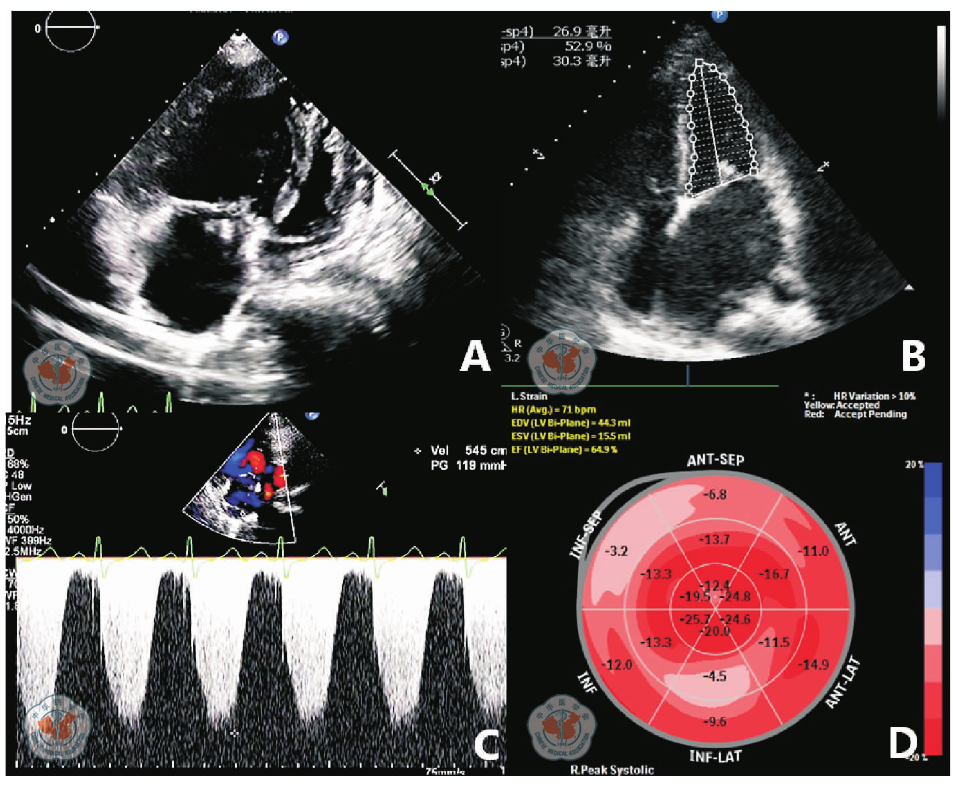

图3 妊娠合并严重心脏病患者剖宫产围术期经胸超声心动图。A为特发性肺高压超声心动图表现,B为风湿性心脏病左室射血分数测量,D为合并肺动脉高压的血流频谱,E为左室功能斑点追踪定量分析